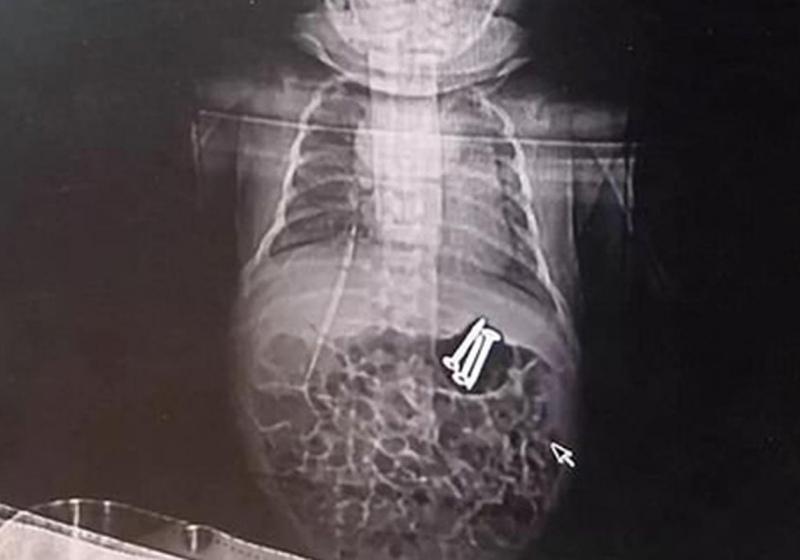

Инцидент произошел в городе Чжэнчжоу. Китаянка оставила дома двух своих детей, так как решила, что старший брат сможет присмотреть за месячным младенцем. Однако когда вернулась домой, то обнаружила, что у малыша изо рта идет пена. Женщина немедленно отнесла его в больницу, где ребенку сделали рентген и обнаружили в желудке три гвоздя, передает Час Пик со ссылкой на зарубежные СМИ.

Врачи предложили матери провести операцию по их извлечению, но предупредили, что трубка эндоскопа может быть слишком широкой для новорожденного. Более узкий инструмент они не могли использовать, так как он не смог бы втянуть гвозди.

Медикам удалось достать гвозди, более того, эндоскопия показала, что в пищеварительном тракте младенца нет порезов. Сейчас ребенок восстанавливается после операции.